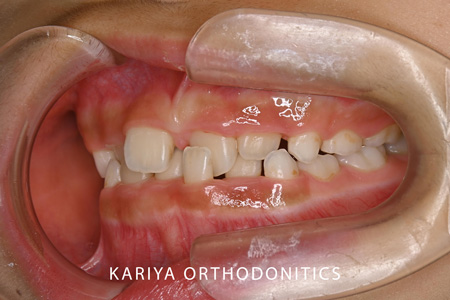

3本の前歯が反対咬合になっている歯並びの1期治療を行いました。

前歯が互い違いになっていると矯正装置がつけずらく、また脱離もしやすいため見た目以上に治療の難易度が上がります。

本症例では、リンガルアーチと補助断線により上顎前歯の唇側傾斜と下顎前歯の舌側傾斜を行いました。

1期治療では、前後的な被蓋関係の改善を行いましたので、2期治療では、垂直的な咬合関係の改善を行ってまいります。